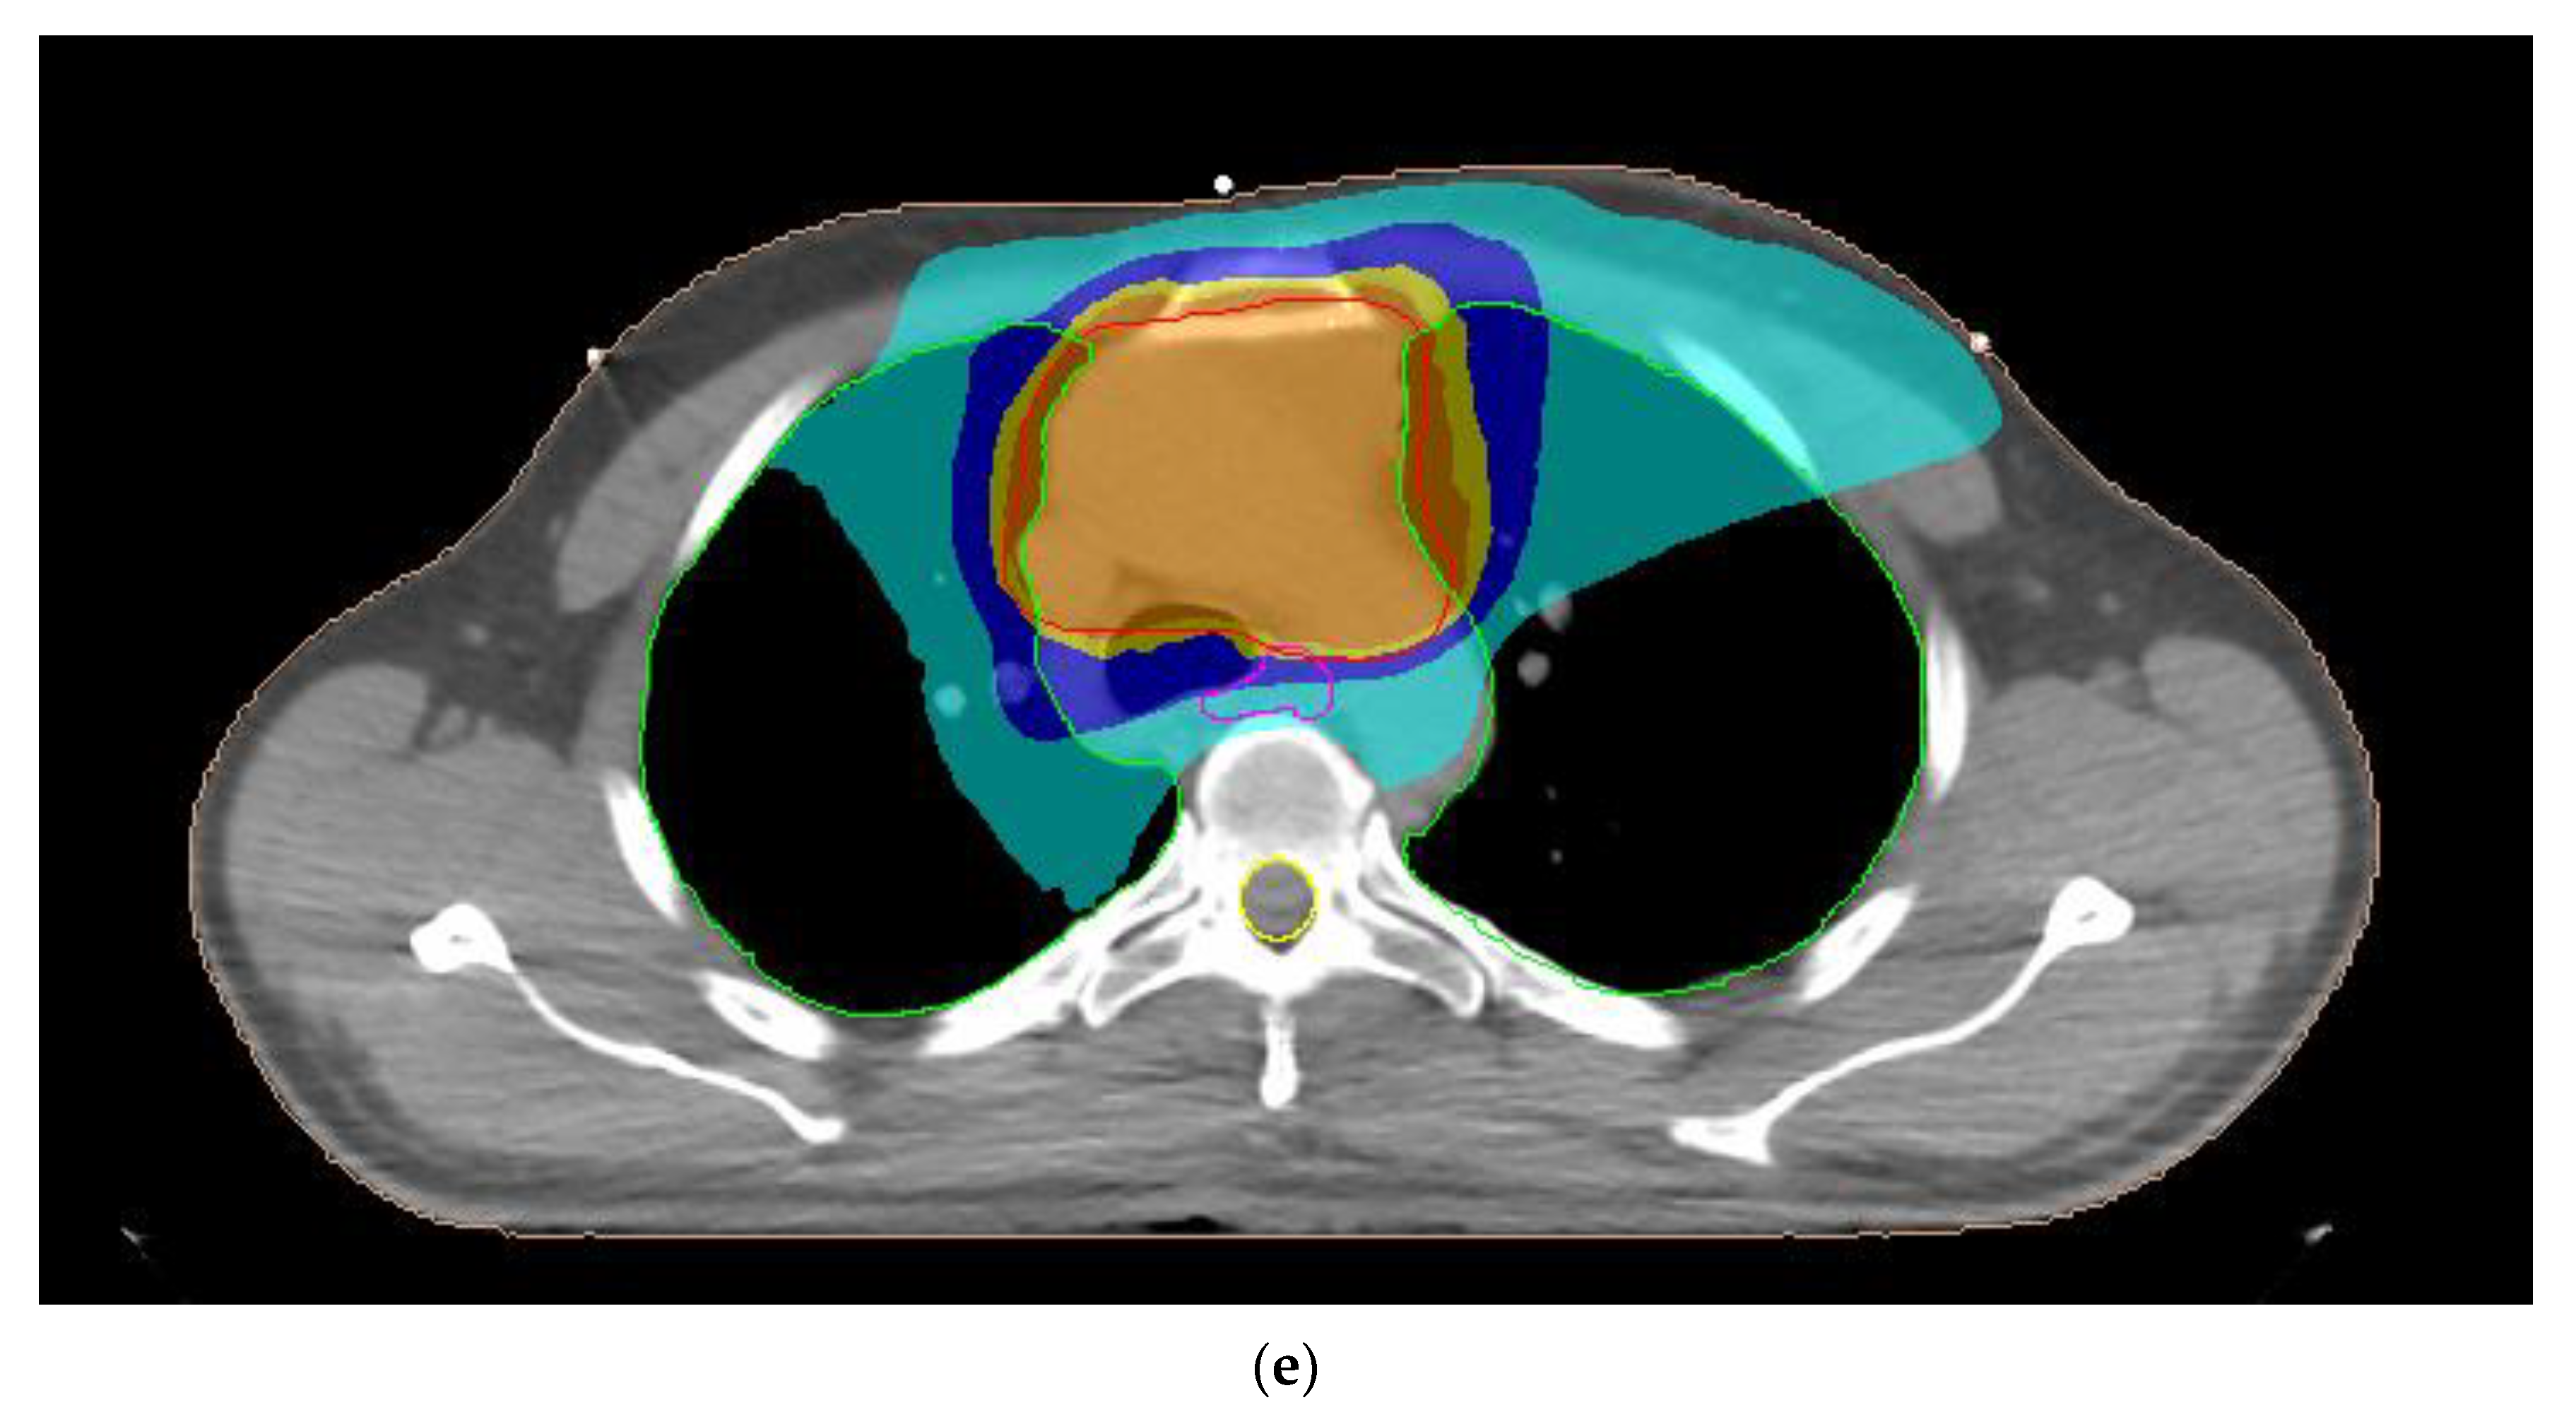

2.2. Treatment Planning